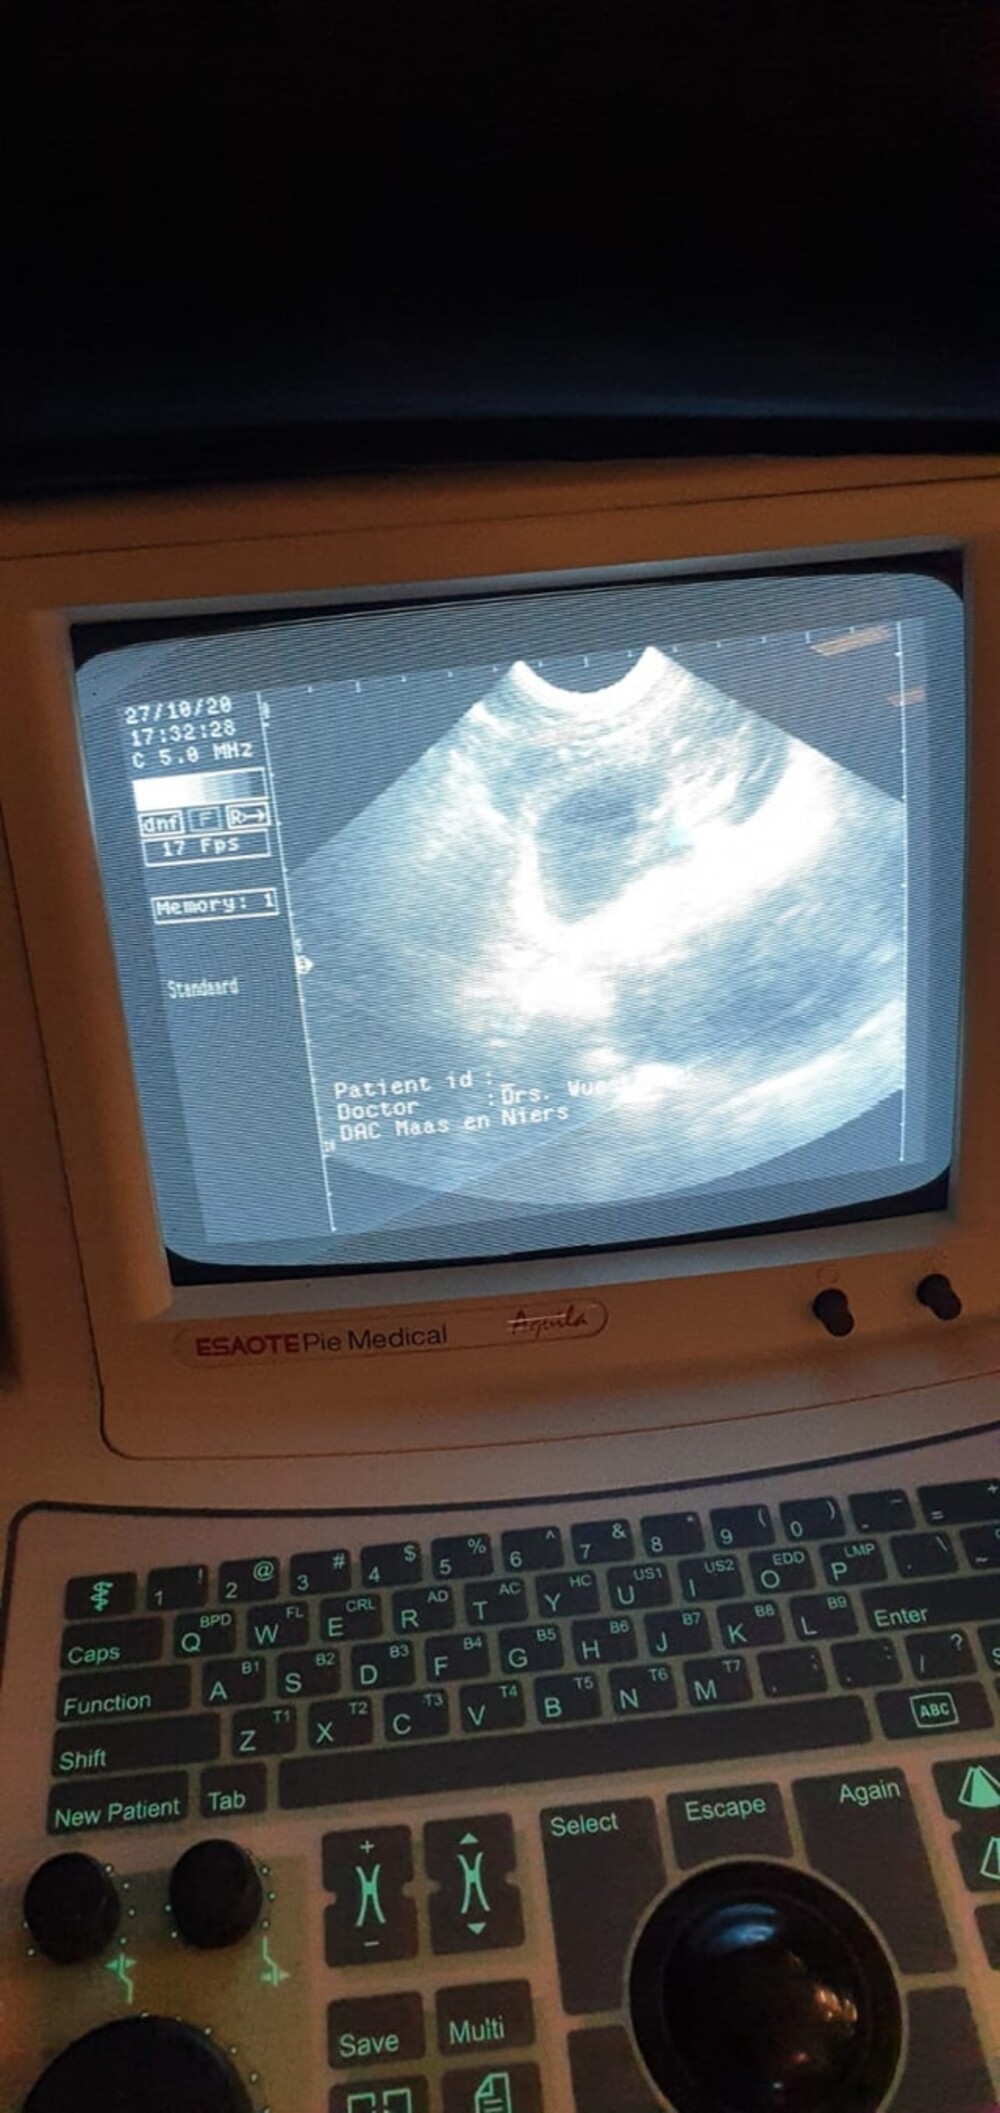

de dierenarts mocht Dakota eerst scheren, dit had ze nog niet eerder meegemaakt, maar ze vondt het niet zo erg, daarna heeft de dierenarts de scan gemaakt:

Ze is drachtig. het blijft moeilijk te zien hoeveel puppy's we kunnen verwachten, maar de dierenarts gaf aan dat we een mooi nest krijgen: niet te groot en niet te klein nest, ze ging uit van 4 a 5 puppy's. Dierenarts verwacht dan ook geen complicaties en een natuurlijke bevalling.